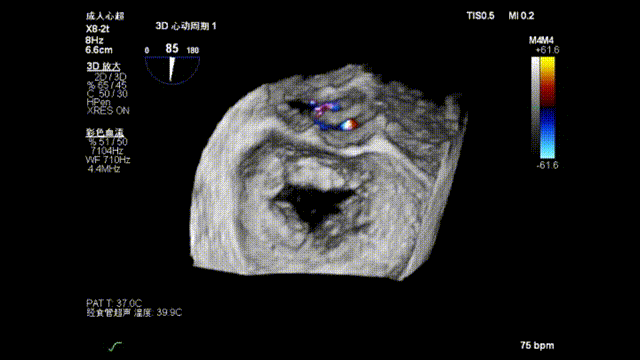

3D enface view示二尖瓣内后叶2偏1区瓣尖可见断裂的腱索呈“连枷样”运动,偏心性返流

3D模式测量二尖瓣瓣口面积5.62cm²术前TEE房间隔高度约4.72cm

3D指示下调整瓣膜夹朝向病变区域

确定瓣膜夹与病变区域垂直后,放下夹片;超声确认前叶后叶都夹合充分,3D检查瓣膜夹位置.